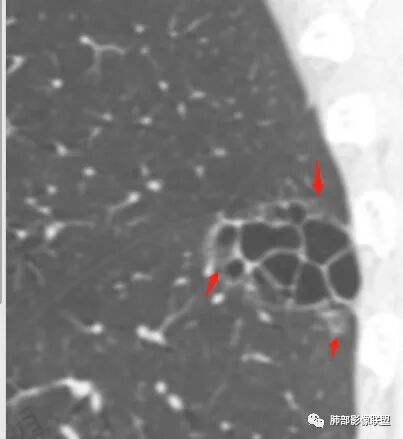

囊腔型肺癌是一种特殊形态的肺癌,病灶边缘或中央存在一个或多个含气的囊腔,其囊腔直径大于5mm(小于5mm的为空泡)、囊壁厚度小于4mm,当影像上难以判断空洞或空腔时,可以笼统定义位于囊腔样病变。囊腔肺癌以腺癌多见,鳞癌少见,早期表现不典型时容易误诊或不被重视。

囊腔型肺癌的诊断要点

1.囊壁是否规则,内壁是否光整。

2.囊壁是否存在不规则增厚或伴有壁结节。这有时需要薄层冠矢状位观察。应留意壁结节及增厚囊壁有无异常强化。

3.囊腔内结构:囊内如果有分隔、支气管及血管穿行应该考虑空腔,而非空洞,这种需要高度怀疑恶性

4.囊腔周围是否有清楚的磨玻璃影,如果有强烈提示腺癌

5.病灶是否有分叶、毛刺、支气管截断、血管集束征、胸膜凹陷征等周围型肺癌的影像征象。应留意同侧肺门及纵隔有无增大淋巴结。